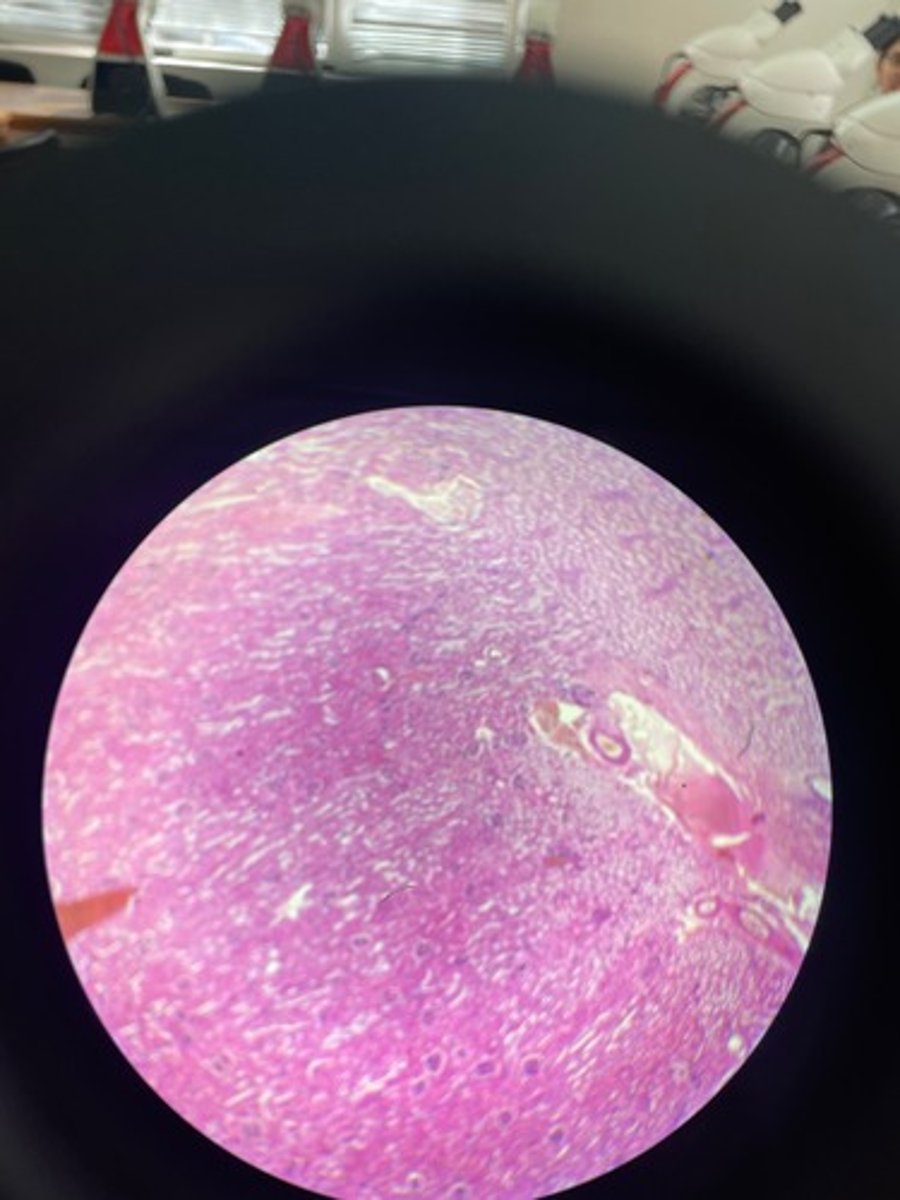

Prostate HE

Prostate HE

Prostate HE

Prostate HE